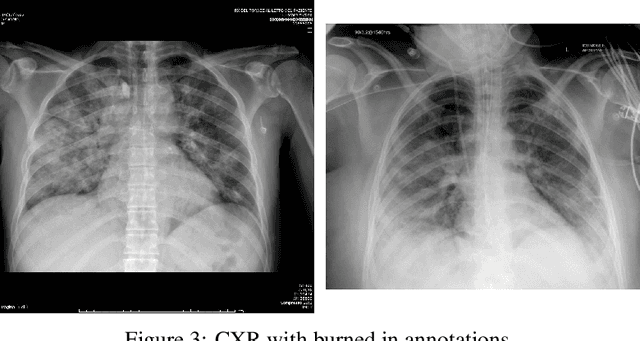

Abstract:The COVID-19 pandemic is undoubtedly one of the biggest public health crises our society has ever faced. This paper's main objectives are to demonstrate the impact of lung segmentation in COVID-19 automatic identification using CXR images and evaluate which contents of the image decisively contribute to the identification. We have performed lung segmentation using a U-Net CNN architecture, and the classification using three well-known CNN architectures: VGG, ResNet, and Inception. To estimate the impact of lung segmentation, we applied some Explainable Artificial Intelligence (XAI), such as LIME and Grad-CAM. To evaluate our approach, we built a database named RYDLS-20-v2, following our previous publication and the COVIDx database guidelines. We evaluated the impact of creating a COVID-19 CXR image database from different sources, called database bias, and the COVID-19 generalization from one database to another, representing our less biased scenario. The experimental results of the segmentation achieved a Jaccard distance of 0.034 and a Dice coefficient of 0.982. In the best and more realistic scenario, we achieved an F1-Score of 0.74 and an area under the ROC curve of 0.9 for COVID-19 identification using segmented CXR images. Further testing and XAI techniques suggest that segmented CXR images represent a much more realistic and less biased performance. More importantly, the experiments conducted show that even after segmentation, there is a strong bias introduced by underlying factors from the data sources, and more efforts regarding the creation of a more significant and comprehensive database still need to be done.

Abstract:The COVID-19 can cause severe pneumonia and is estimated to have a high impact on the healthcare system. The standard image diagnosis tests for pneumonia are chest X-ray (CXR) and computed tomography (CT) scan. CXR are useful in because it is cheaper, faster and more widespread than CT. This study aims to identify pneumonia caused by COVID-19 from other types and also healthy lungs using only CXR images. In order to achieve the objectives, we have proposed a classification schema considering the multi-class and hierarchical perspectives, since pneumonia can be structured as a hierarchy. Given the natural data imbalance in this domain, we also proposed the use of resampling algorithms in order to re-balance the classes distribution. Our classification schema extract features using some well-known texture descriptors and also using a pre-trained CNN model. We also explored early and late fusion techniques in order to leverage the strength of multiple texture descriptors and base classifiers at once. To evaluate the approach, we composed a database, named RYDLS-20, containing CXR images of pneumonia caused by different pathogens as well as CXR images of healthy lungs. The classes distribution follows a real-world scenario in which some pathogens are more common than others. The proposed approach achieved a macro-avg F1-Score of 0.65 using a multi-class approach and a F1-Score of 0.89 for the COVID-19 identification in the hierarchical classification scenario. As far as we know, we achieved the best nominal rate obtained for COVID-19 identification in an unbalanced environment with more than three classes. We must also highlight the novel proposed hierarchical classification approach for this task, which considers the types of pneumonia caused by the different pathogens and lead us to the best COVID-19 recognition rate obtained here.